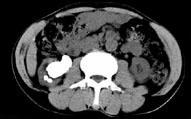

- 多项选择题男,53岁, 反复右侧腰部隐痛不适2年余,CT如图所示, 下列说法正确的是 ( )

A、右肾多发结石

B、右肾铸型结石

C、右肾钙化

D、右肾自截

E、部分肾盏有扩张积液